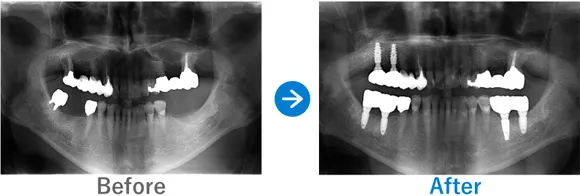

ほとんどの歯が残存していないケース

Case1

歯が1本もない状態からインプラント治療で噛める幸せを取り戻された方

歯が1本もない状態、10年以上前から上下総義歯(総入れ歯)

上顎ALLON6、下顎ALLON4、

リオペ上顎追加埋入ザイゴマインプラント2本

9,823,000円(上顎6,248,000円、下顎3,575,000円/内訳:上顎オールオン6(ノーベルザイゴマインプラント2本・ストローマンインプラント4本)、下顎オールオン4(ストローマンインプラント4本)3Dモデルガイド*、仮歯、セデーション、ボツリヌストキシン注射、3D模型、保証10年)

来院の背景

10年以上前から上下義歯(総入れ歯)だが、義歯が痛くて、食事に困っている。他院にて仮義歯を作ってもらっていたが担当医が辞めたこともあり、インプラントを検討。ネットで探して退院。痛みなく食事がしたい。

治療結果

上下ALLON4、右上5、左上3、リオペザイゴマインプラント2本追加順調の経過、治療終了、メンテナンス来院。インプラントで噛めるようになり、喜んでいただいた。しっかりセルフケアを頑張っておられます。お顔の表情も明るくなられて、気持ちも前向きに過ごされています。